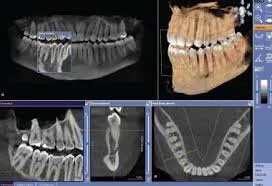

SIRONA GALILEOS

Dental cone beam computed tomography (CT) is a special type of x-ray machine used in situations where regular dental or facial x-rays are not sufficient. It is not used routinely because the radiation exposure from this scanner is significantly more than regular dental x-rays. See the Safety page for more information about x-rays. This type of CT scanner uses a special type of technology to generate three dimensional (3-D) images of dental structures, soft tissues, nerve paths and bone in the craniofacial region in a single scan. Images obtained with cone beam CT allow for more precise treatment planning.

Cone beam CT is not the same as conventional CT. However, dental cone beam CT can be used to produce images that are similar to those produced by conventional CT imaging.

With cone beam CT, an x-ray beam in the shape of a cone is moved around the patient to produce a large number of images, also called views. CT scans and cone beam CT both produce high-quality images.

Cone beam CT provides detailed images of the bone and is performed to evaluate diseases of the jaw, dentition, bony structures of the face, nasal cavity and sinuses. It does not provide the full diagnostic information available with conventional CT, particularly in evaluation of soft tissue structures such as muscles, lymph nodes, glands and nerves. However, cone beam CT has the advantage of lower radiation exposure compared to conventional CT.